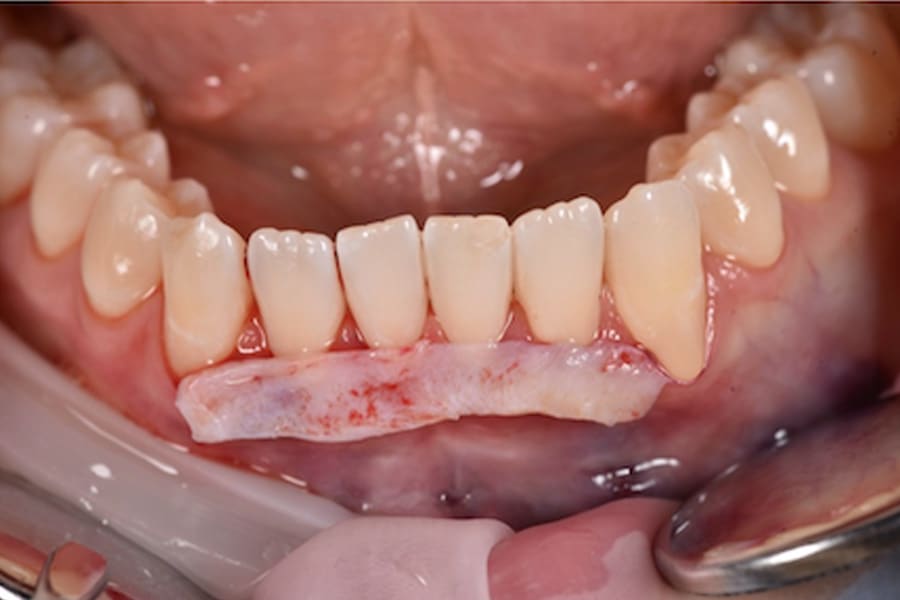

Periodontal Management and Thin Phenotypes

In thin phenotypes with early recessions, minimally invasive tunneling with CTG (with enamel matrix proteins on exposed roots when indicated) can increase soft-tissue thickness and support long-term stability after orthodontic tooth movement.12-16 (Figure 14 through Figure 17)